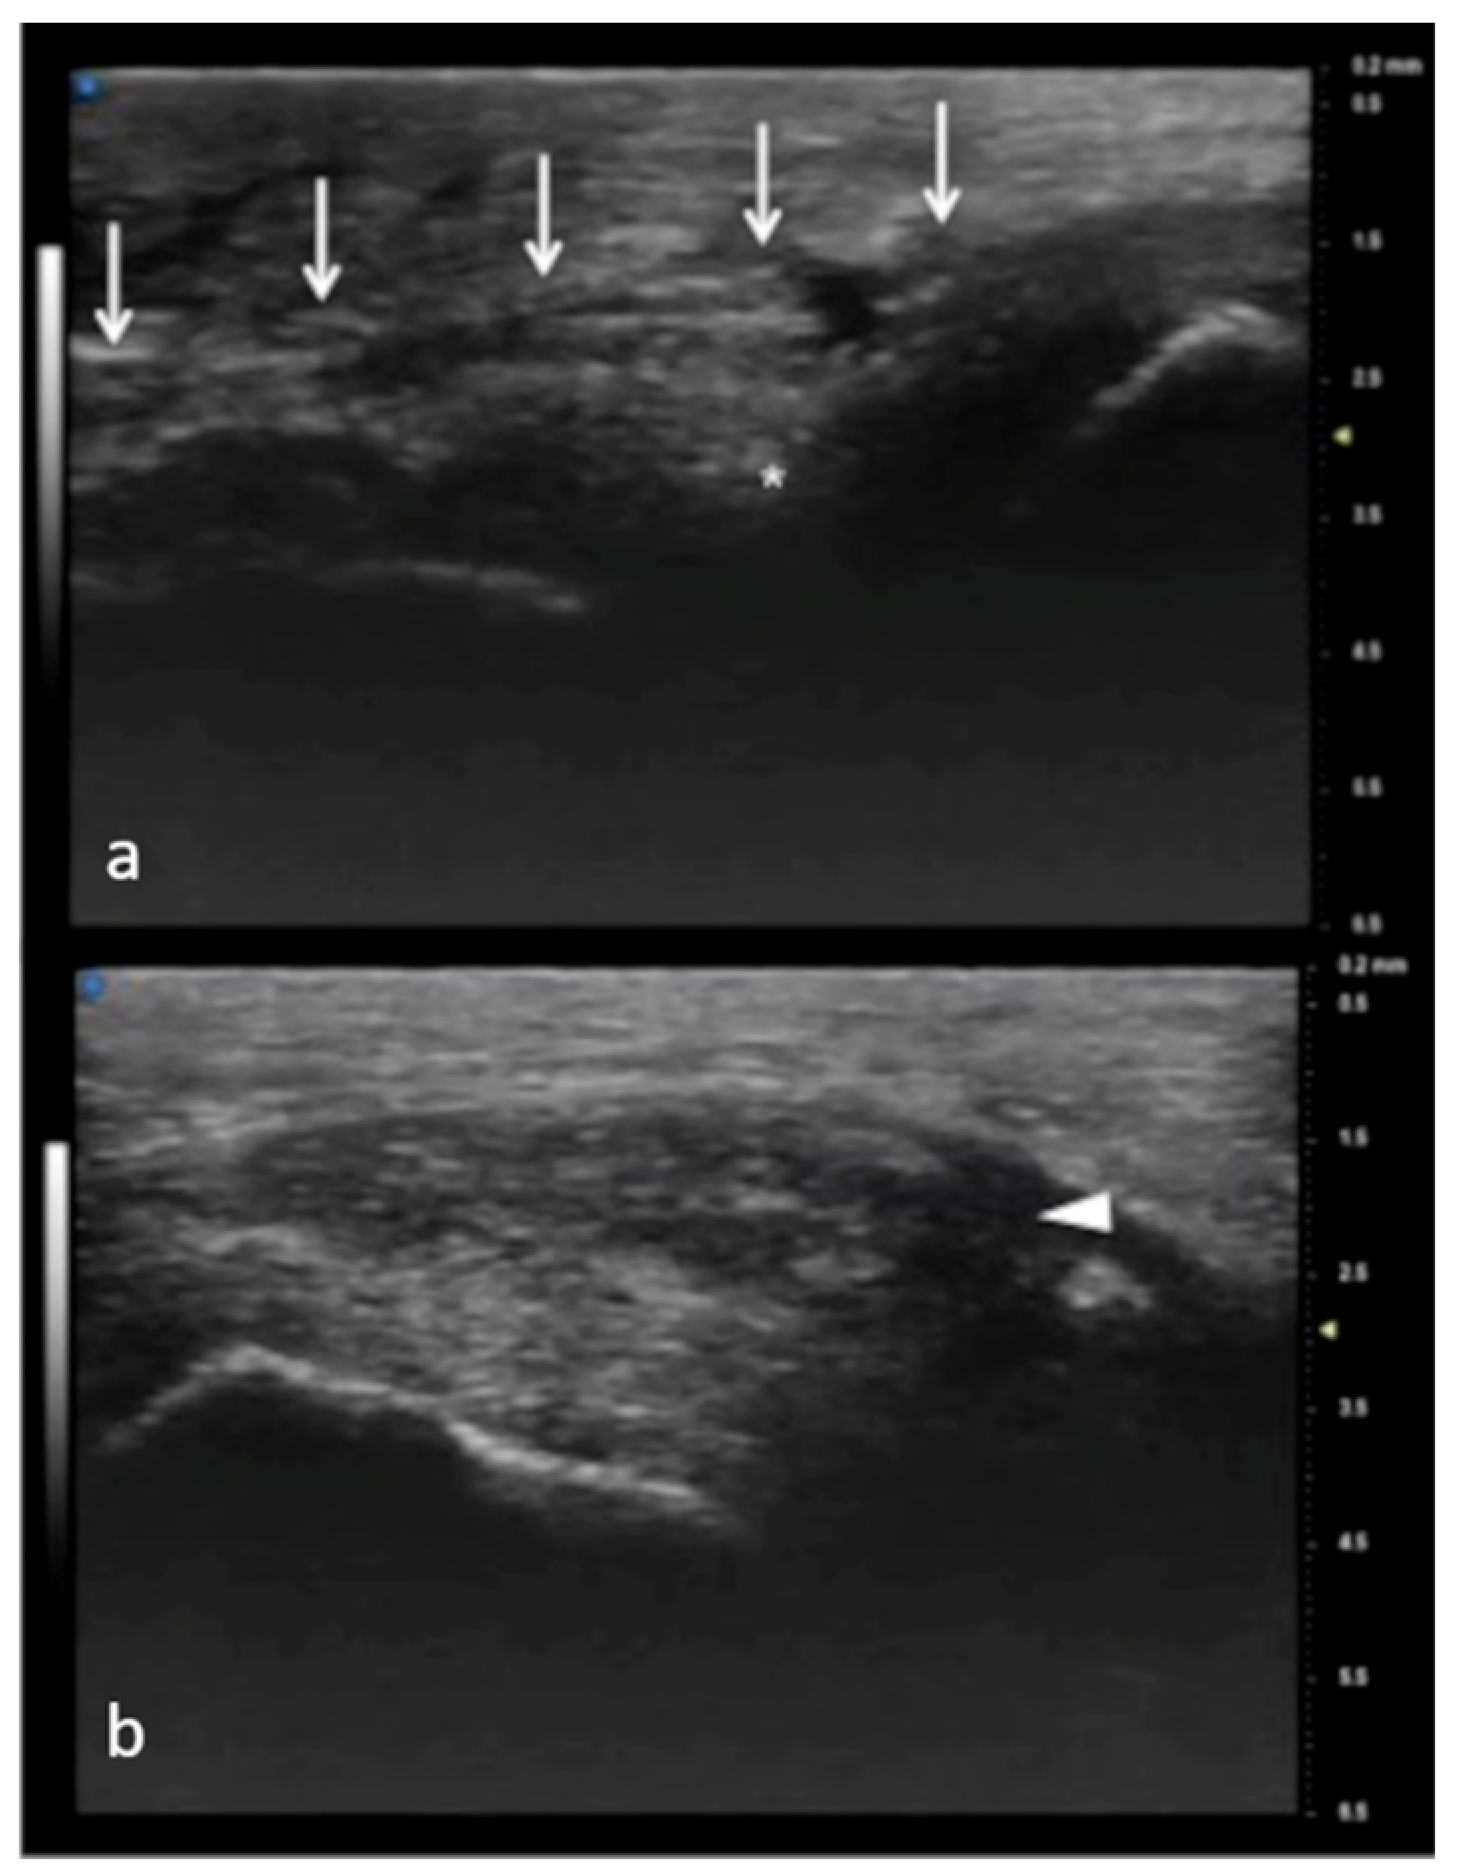

Figure 7.

Full-thickness UCL tear. In (a), normal appearance of adductor pollicis aponeurosis (white arrows) and below the ulnar collateral ligament (asterisk) of the first metacarpophalangeal joint. In (b), the non-visualization of the ulnar collateral ligament and the presence of a mass-like area (arrowhead) proximal to the joint have high accuracy in depicting a displaced full-thickness ligament tear.

Figure 8.

Same patient as in Figure 7. 1.5 T MRI shows a mass-like area (arrowhead) proximal to the joint representing the injured and displaced ligament in (a). In (b), the contralateral metacarpal phalangeal joint of the thumb. M: metacarpal head.